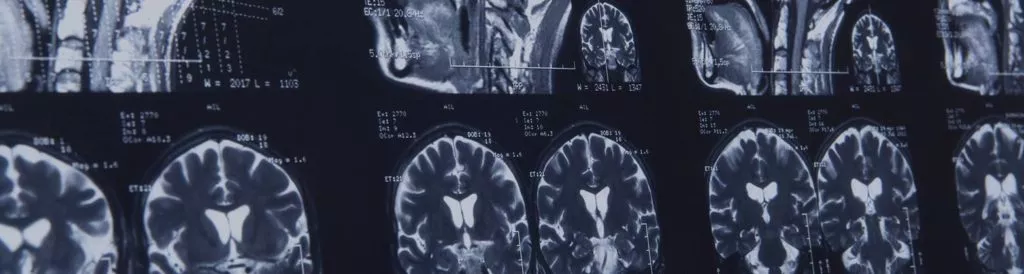

What is a Traumatic Brain Injury?

A forceful blow to the head causes traumatic Brain Injury (TBI). It can result from blunt force (such as hitting the head on the ground) or penetrating trauma (such as a bullet). The strength of the impact can cause the brain to shift and collide with the skull’s inside, causing bruising, bleeding, and swelling. It is common for a victim to have a fractured skull with TBI; however, it does not always fracture.